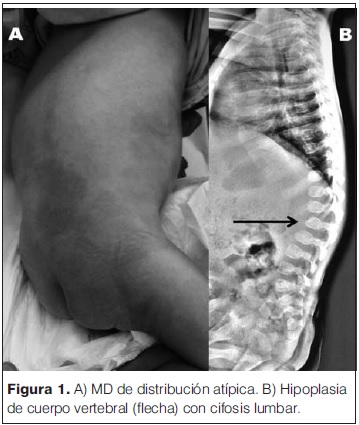

Lactante de 9 meses, sexo masculino, referido al hospital para evaluación por hipotonía, letargia y retraso global del desarrollo. Era un niño de raza caucasiana, producto de un primer embarazo sin complicaciones, de padres sanos adolescentes, no consanguíneos, sin antecedentes familiares de interés. Nacido a término por parto vaginal sin complicaciones, vigoroso, antropometría dentro de percentiles normales, sin patología perinatal a destacar. Sus primeros tres meses de vida presenta un desarrollo normal, luego de lo cual se objetiva un deterioro progresivo de las conductas adquiridas, presentando al momento de la consulta un severo retraso global del desarrollo. Al examen se destaca desnutrición severa, fascies toscas con cuello corto, puente nasal bajo, nariz ancha y filtrum largo, hipertrofia gingival, hepatomegalia leve, hidrocele bilateral, cifosis lumbar, no sostén cefálico, escasa fijación y seguimiento ocular, hipotonía global severa con reflejos osteotendinosos vivos y trastorno en la succión y deglución. El fondo de ojo mostró una retina pálida, no se evidenció mancha rojo cereza. A nivel cutáneo presenta una extensa mancha mongólica de color azulado y de distribución difusa a nivel del sector posterior de tronco y axilas (figura 1A). De la paraclínica se destaca la normalidad de: resonancia magnética de cráneo, perfil tiroideo, gasometría venosa, función renal y hepático, amoniemia, lactacidemia, aminoácidos en sangre, ácidos orgánicos en orina, uricemia, creatina quinasa en sangre y mucopolisacáridos en orina. La serología para citomegalovirus, rubeola y toxoplasmosis negativas. Los potenciales evocados visuales y auditivos presentaron una severa disfunción bilateral. En el frotis de sangre periférica se objetivaron linfocitos vacuolados. La radiografía de columna de perfil mostró una cifosis lumbar y vértebras con hipoplasia del sector ántero-superior del cuerpo vertebral (figura 1B). La presencia de oligosacáridos elevados en orina y la actividad deficiente de b-galactosidasa en sangre, presentando valores de 1,6 nmol/h/L (normal 30,4–128,4 nmol/h/L), confirmó el diagnóstico de gangliosidosis GM1. El paciente falleció a los 15 meses de vida.